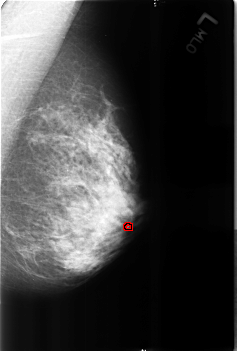

B_3168_1.LEFT_MLO

LEFT_MLO LINES 4552 PIXELS_PER_LINE 3072 BITS_PER_PIXEL 12 RESOLUTION 50 OVERLAY

FILE: B_3168_1.LEFT_MLO.OVERLAY

TOTAL_ABNORMALITIES 1

ABNORMALITY 1

LESION_TYPE CALCIFICATION TYPE COARSE-LUCENT_CENTER DISTRIBUTION N/A

ASSESSMENT 2

SUBTLETY 3

PATHOLOGY BENIGN_WITHOUT_CALLBACK

TOTAL_OUTLINES 1

BOUNDARY